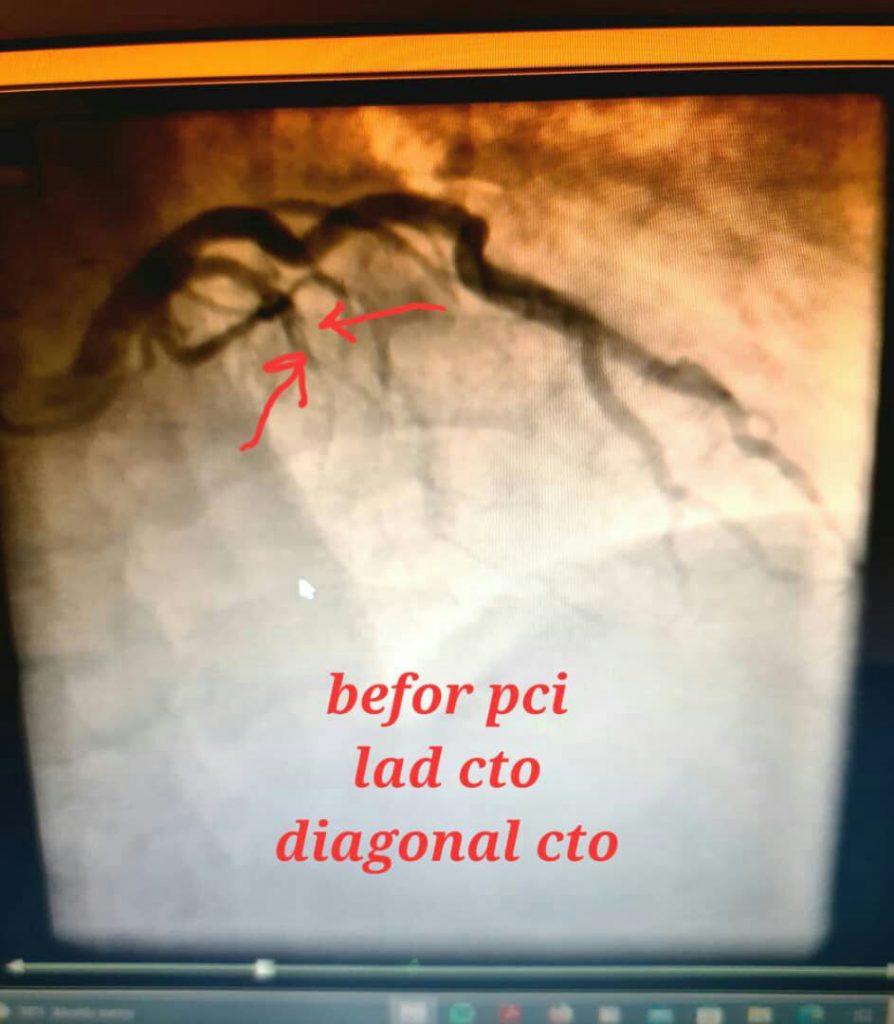

آنژیوپلاستی عروق تنگ یا کاملا مسدود قبلی , والووپلاستی

درمان انسداد کامل عروق قلبی بدون نیاز به عمل جراحی باز